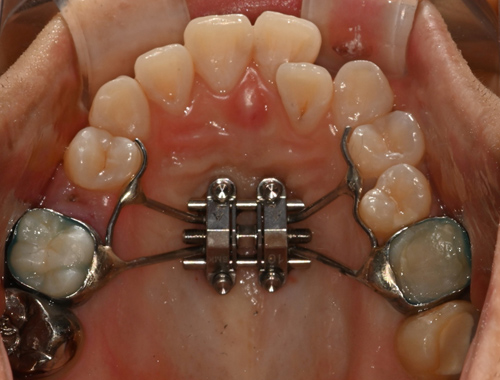

비수술 악궁확장 치료 MARPE (Miniscrew-assisted rapid palatal expansion)

덧니의 근본적인 원인은 치아 크기에 비해서 뼈의 크기가 작기 때문입니다.

청소년기가 지나간 성인에서는 뼈의 크기를 늘리기 어렵지만 이지민 대표원장은 가능합니다.

이지민 원장은 성인 비발치 교정의 핵심인 비수술 악궁 확장 가능성을, 직접 연구한 논문 결과를 바탕으로 사전에 정밀 분석·예측합니다.